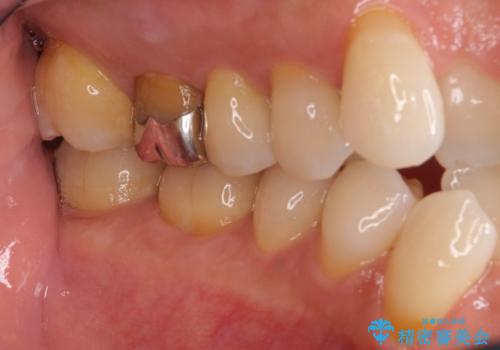

- 2年ほど放置していた左上の仮歯がとれたことをきっかけにご来院された患者様です。

セラミック治療がご希望でしたが、ときどき歯肉が腫れるということで根管治療もご希望されました。

左上の仮歯を2年使用して穴があいて外れたことをきっかけにご来院されました。

レントゲン上からも、歯の中(根管)が汚れている可能性があることをご説明したところ、根管治療からやり直しをすることになりました。